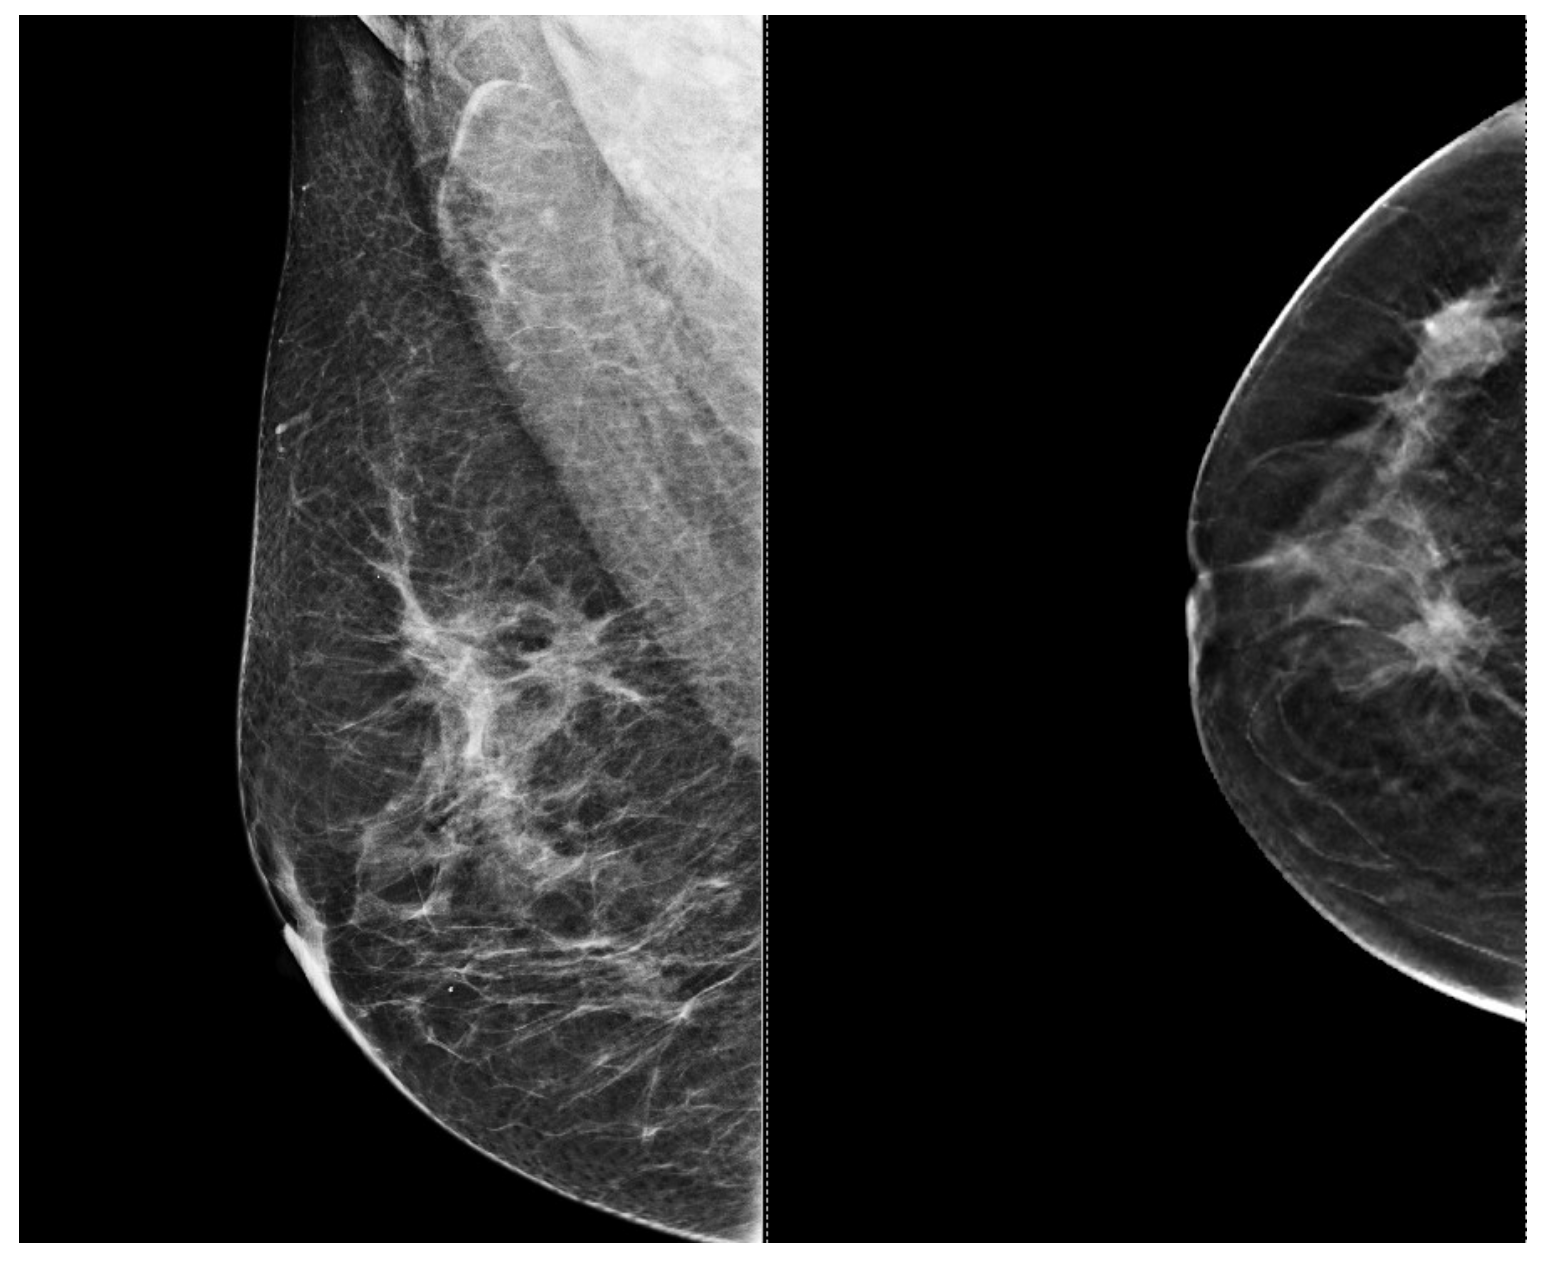

5.3. Low Ability to Detect Microcalcifications

5.4. Limited Performance in High-Risk or Dense Breast Tissue